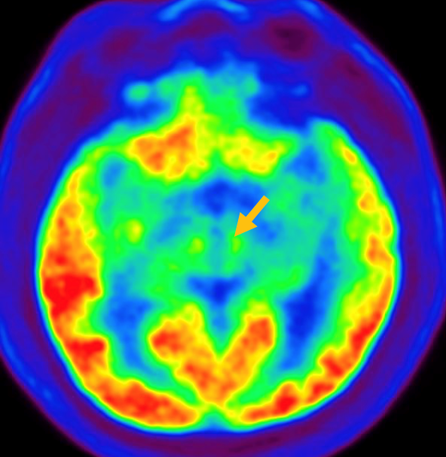

다계통 위축이란 뇌의 다양한 계통에서 위축이 발생하는 것을 의미합니다. 파킨슨 증상이 있으면서 질병 초기에 소변 장애나 기립성 저혈압으로 인한 어지러움이 두드러지게 나타나는 경우, 보행 시 비틀거림이나 구음 장애와 같은 소뇌 위축에 따른 운동 실조 증상이 나타나는 경우, 꿈에서 하는 행동을 수면 중에 보이는 렘수면 행동 장애가 동반되는 경우 다계통 위축을 의심합니다. 다계통 위축은 파킨슨병과 달리 안정 시 떨림이 잘 보이지 않고, 증상이 대칭적인 경우가 많으며, 진행이 빠르며, 레보도파와 같은 항파킨슨 약제에 잘 반응하지 않습니다. 다계통 위축은 뇌 자기공명영상(MRI)에서 교뇌에 십자 모양의 고음영이 나타날 수 있는데, 이를 십자무늬 빵(hot cross bun) 징후라고 합니다. 또한 초기에서는 뇌 자기공명영상(MRI)이 정상으로 보이더라도 뇌포도당 양전자 단층촬영(PET)에서는 소뇌 또는 기저핵의 대사 기능이 저하된 상태가 관찰될 수 있습니다. 이러한 영상 소견은 특징적인 임상 증상과 함께 진단에 참고할 수 있습니다.

[다계통위축 환자의 뇌자기공명영상에서 확인되는 십자무늬빵 징후]

[다계통위축 환자의 뇌포도당 양전자 단층 촬영에서 확인되는 소뇌의 대사 기능 저하]3. 피질 기저핵 변성(Corticobasal degeneration)